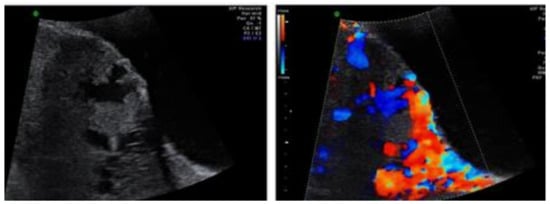

2. Case 1: History, Investigations, Treatment, and Outcomes